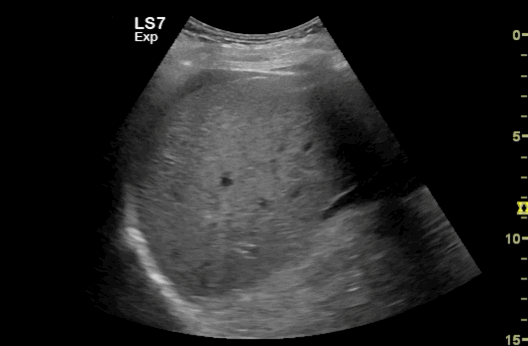

- Is free fluid present around the liver ?

Reminder: Ensure to ‘sweep’ / tilt the transducer around the kidney to thoroughly assess the potential space between the liver and kidney for complete evaluation.